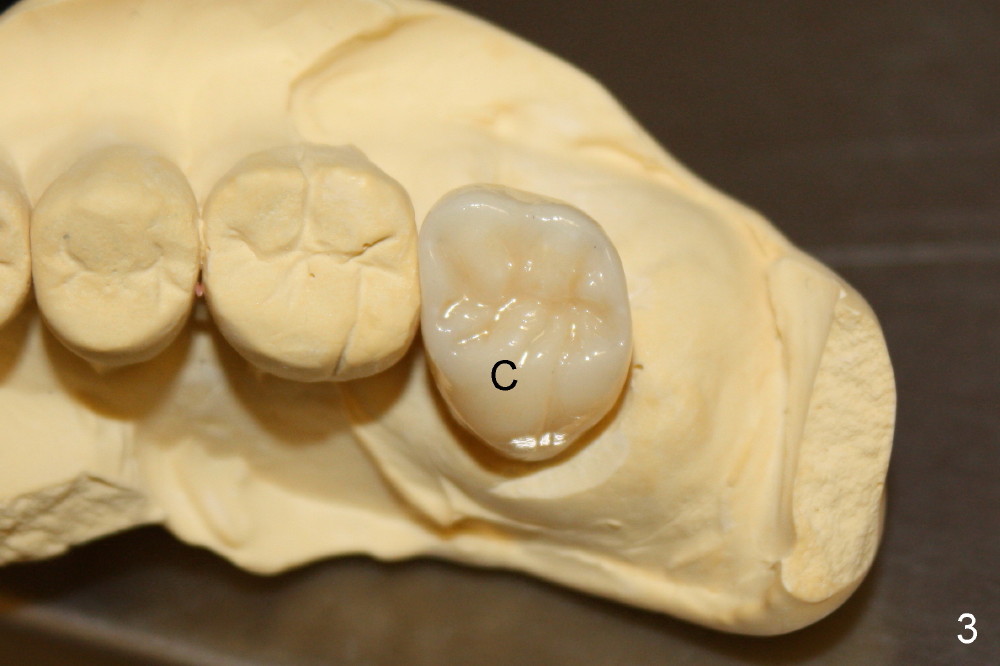

图一显示即刻植牙(箭头)术后接近三个月,明显偏向鄂侧。术后四个月,装上台基(图二:A),在种植体和台基上面制备牙冠,戴上牙冠(图三:C),咬合面挺正常。颊侧远中观(图四)显示这个牙冠有悬臂桥味道,但是这个上颌第二磨牙功能尖在鄂侧(P; B:颊侧),使用Zirconia材料做牙冠,估计不会出现陶瓷断裂问题。直径大的种植体和台基共同支撑牙冠(图二),所以后者也不容易脱落。